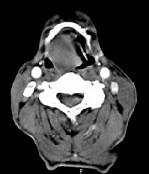

问题 男,74岁,咽喉部不适一年余,近两三个月咽喉疼痛,吞咽困难,CT如图所示,最可能诊断是()

选项 A.喉癌 B.会厌癌 C.声带癌 D.声门下区癌 E.跨声门型癌

答案 B